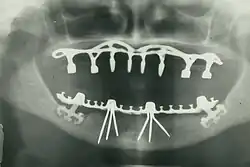

Im November 1895 entdeckte Wilhelm Conrad Röntgen die später nach ihm benannten Röntgenstrahlen, die die Untersuchung des Kiefers vereinfachten. Als Mittel zur örtlichen Betäubung von Zahnschmerzen wurde im Jahre 1905 das Lokalanästhetikum Procain von den deutschen Chemikern Alfred Einhorn und Emil Uhlfelder entwickelt, die dem Wirkstoff den Namen Novocain (lateinische Wortschöpfung für „Neues Cocain“) zuordneten. Damit waren die Grundlagen für eine moderne Diagnostik und Therapie gelegt. Die Zahnheilkunde erlebte daraufhin einen rasanten Fortschritt: von der Entwicklung zahlreicher oralchirurgischer Verfahren bis zur Anfertigung von Zahnersatz mittels CAD/CAM-Verfahren. Parallel zum Fortschritt der wissenschaftlichen Zahnheilkunde entwickelte sich das Berufsbild, was in der Geschichte des Zahnarztberufs dargestellt wird. Daneben entwickelte sich die Tierzahnheilkunde, die sich entsprechend modifizierter Verfahren der allgemeinen Zahnheilkunde bedient.